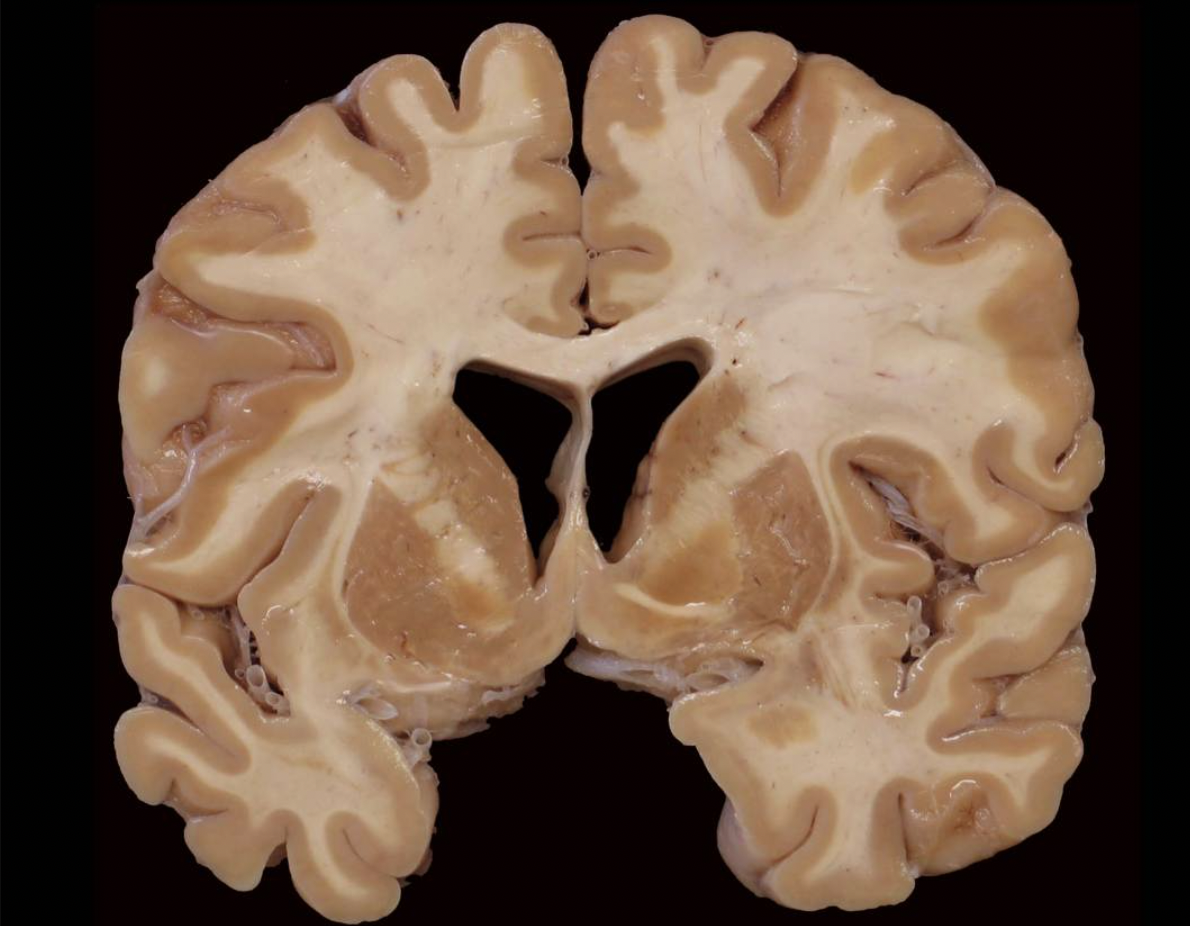

Inspect this photograph below and take a moment to orient yourself to the plane of section and the approximate position of this slab in the brain. Got it?

Given where you think this slab came from in the brain, which of the following gyri or lobules are visible in this slab?

A. precuneus gyrus

B. inferior parietal lobule

C. superior parietal lobule

D. superior frontal gyrus

E. paracentral lobule